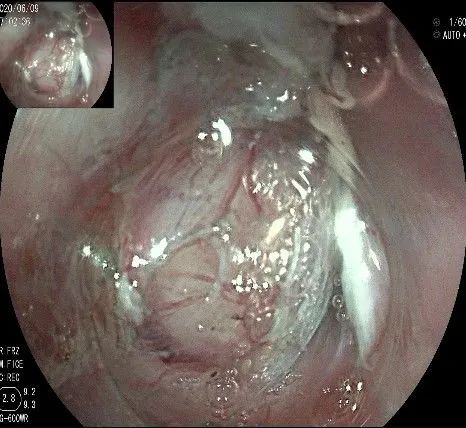

倒镜观察,可见贲门部一个明显的隆起,中央部分的凹陷,是4天前取活检留下的。

我们的思路:病变长径约2.0cm,位置活动,倒镜后先在胃底侧粘膜下注射,使病变向食管腔方向抬举,然后再在食管腔内做粘膜下注射切开,以获得一个好的术野,果然,注射后粘膜抬举明显,瘤体被挤向口侧。

正镜观察,瘤体就在贲门部齿状线的下方。

在食管腔内,瘤体的两侧行粘膜下注射后,在瘤体顶部纵向自口侧向肛侧切开食管粘膜。

向下一直切开至齿状线处,白色为鳞状上皮,红色为腺上皮,颗粒样的部分,就是炎性息肉。切开后可见瘤体为白色,表面有血管网,质地较韧。